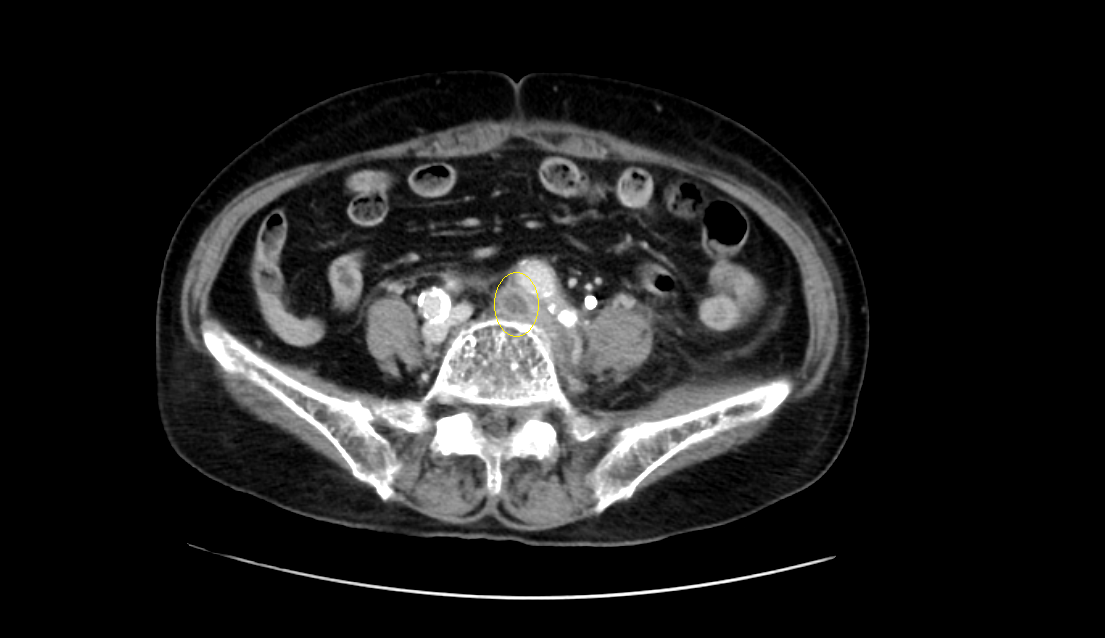

영상은 머리에 가까운 복부에서 다리 쪽으로 가는 순서로 나열하였다.

CT영상을 보면 좌측 장골정맥과 우측 장골동맥이 교차하는 지점에서부터 다리 말단 쪽으로 내려가며, 총장골정맥-외장골정맥-총대퇴정맥-표대대퇴정맥-오금정맥-경골정맥까지 혈전이 차있는 모습을 확인할 수 있었다.

Acute DVT, left CIV, EIV, IIV, CFV, SFV, popliteal and crural veins with compression of left CIV between vertebra and right CIA, c/w acute DVT with May Thurner syndrome.